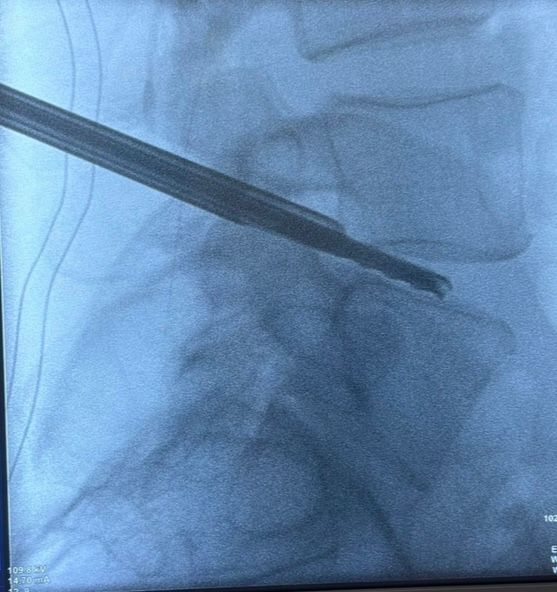

Starszy Asystent w Klinicznym Oddziale Neurochirurgicznym oraz Poradni Neurochirurgii Wojewódzkiego Szpitala Specjalistycznego im. św. Barbary nr 5 w Sosnowcu. Konsultant Kliniki Neurologii Szpitala Klinicznego nr 1 w Zabrzu. Absolwent Wydziału Lekarskiego Śląskiego Uniwersytetu Medycznego w Zabrzu. Staż podyplomowy odbył w latach 2010-2011 w Oddziale Neurochirurgii WSS nr 4 w Bytomiu. W 2018r. złożył egzamin specjalizacyjny po zakończeniu szkolenia w ramach rezydentury w WCM Opole. W 2019 roku uzyskał stopień doktora nauk medycznych. Specjalizuje się w kompleksowym leczeniu schorzeń kręgosłupa (dyskopatia, stenoza kanału kręgowego, kręgozmyk) oraz neuroonkologii. Szczególny zakres działań medycznych to nowoczesne, małoinwazyjne operacje kręgosłupa z wykorzystaniem technik endoskopowych (mikrodiscektomia - implanty rozprężalne), przezskórnych stabilizacji oraz mikrochirurgicznych dekompresji. Wykonuje procedury iniekcyjne; discoGEL, GelSTIX, kriolezje oraz blokady przeciwbólowe kręgosłupa odcinka szyjnego, lędźwiowo-krzyżowego a także stawów krzyżowo-biodrowych, które odgrywają istotną rolę w procesie diagnostyczno-leczniczym wielu zespołów bólowych. Na co dzień przeprowadza operacje w ramach kontraktu z NFZ. Członek Polskiego Towarzystwa Neurochirurgów oraz Polskiego Towarzystwa Chirurgii Kręgosłupa. Uczestnik wielu krajowych i zagranicznych kursów neurochirurgicznych, m.in. w Czechach, Słowacji, Niemczech, Włoszech, Danii, Austrii, Szwajcarii i USA. Autor licznych publikacji naukowych.

Zdjęcia i filmy